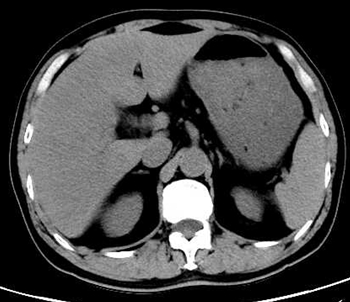

1 病例资料患者,男性,61岁,1 d前(2020-10-9 10点左右)因“无明显诱因出现持续性腹痛”,至外院急诊就诊,腹部CT提示无明显急诊征象(图 1)。实验室检查:白细胞7.25×109/L,中性粒细胞比率75.5%,淋巴细胞比率19.3%,生化提示天门冬氨酸氨基转移酶108 U/L,淀粉酶103 U/L,肌酐73 µmol/L,C-反应蛋白2.4 mg/L,给予解痉、消炎、止痛等对症治疗后出现呕吐、畏寒发热,体温最高超39℃,降温后回家,仍有腹痛、呼吸急促,自行服用三九胃泰。

| 图 1 患者全腹部CT平扫未见明显急诊征象 |